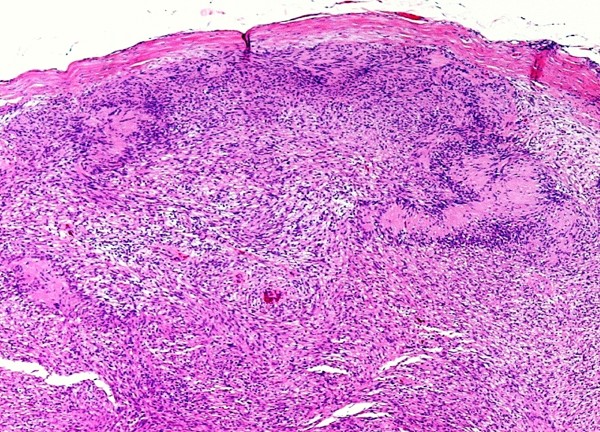

上皮样恶性神经鞘瘤

图片尺寸1181x945